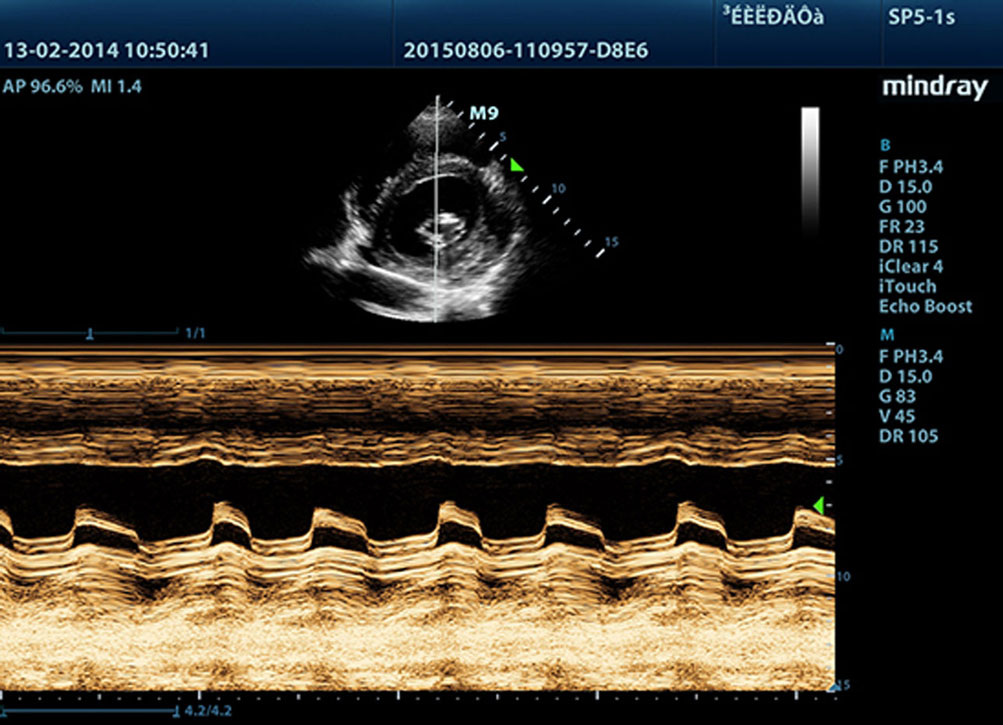

Free Xros M?

Modo M anatĂłmico permite realizar las observaciones y medidas anatĂłmicamente precisas independientemente de la orientaciĂłn. Provee mejores imĂĄgenes a travĂ©s de la visualizaciĂłn simultĂĄnea de hasta 3 lĂneas M.